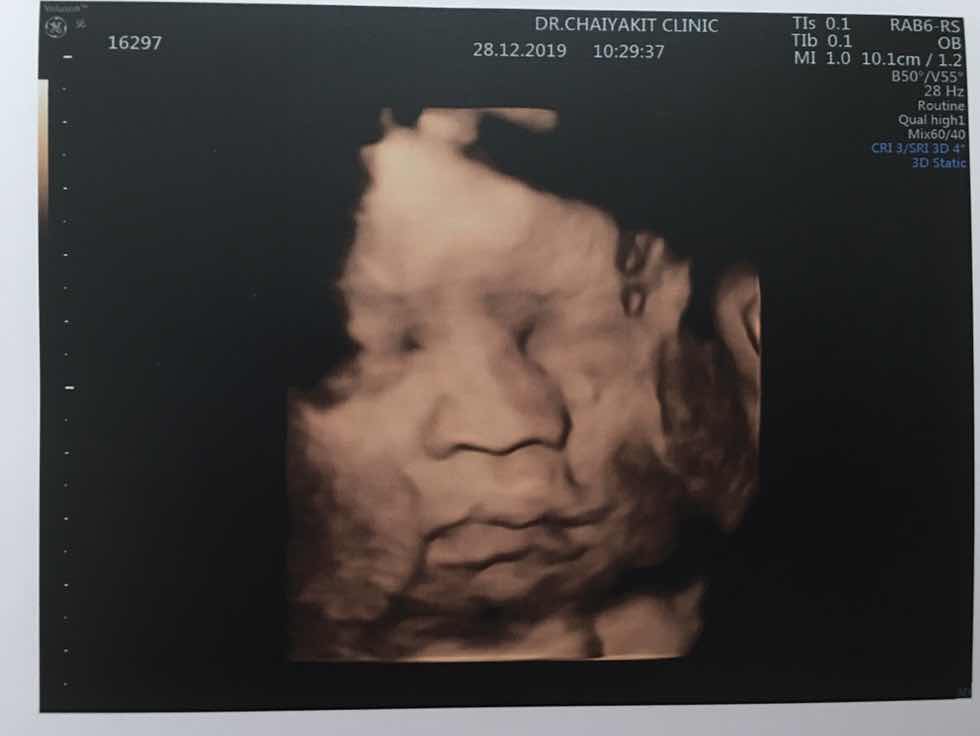

28 w ค่ะ